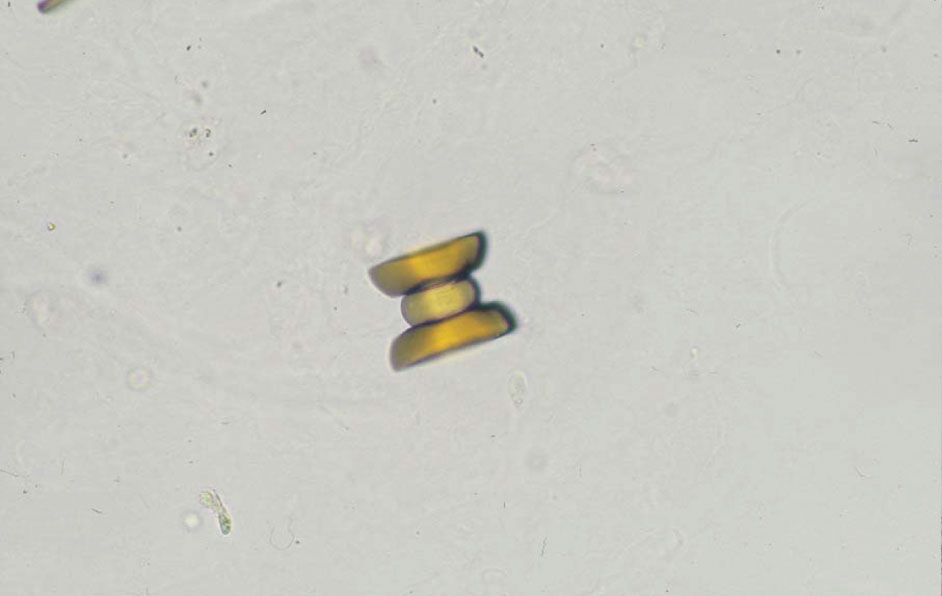

尿酸結晶 40× 無染色

Uric acid crystal 40× No staining

黄褐色で亜鈴状(鉄アレイ状)の結晶である。pH 5.5

A yellowish brown dumbbell-shaped crystal. pH 5.5